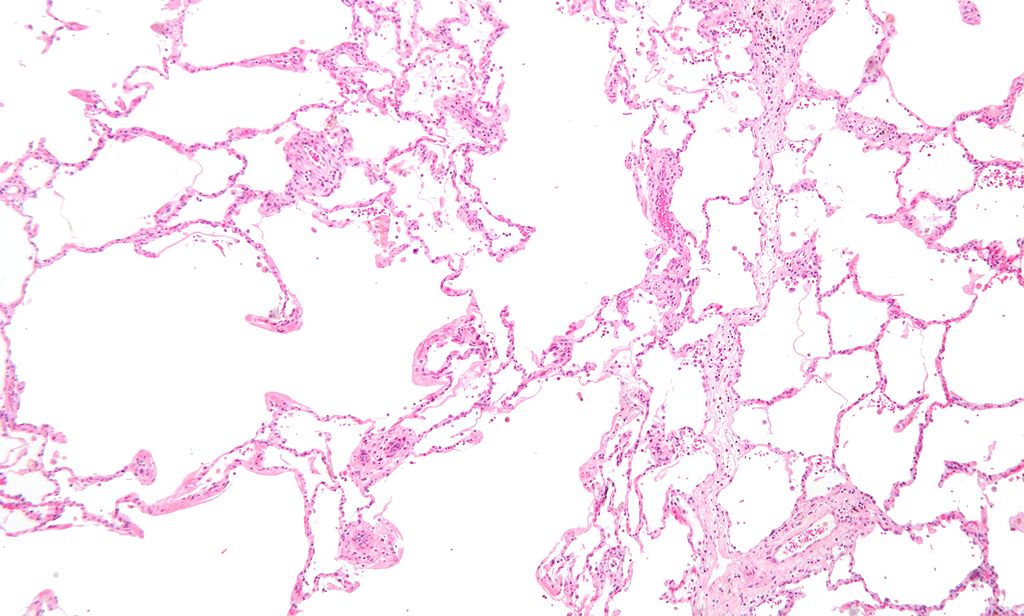

Restrictive Lung Diseases Pathology. Low magnification micrograph of emphysema. H&E stain. The left of image shows severe emphysema (large empty spaces). The lung tissue on the right of the image has relative preservation of the alveoli. The top of the image is very near the pleural surface. Nephron. Not altered. CC BY-SA 3.0